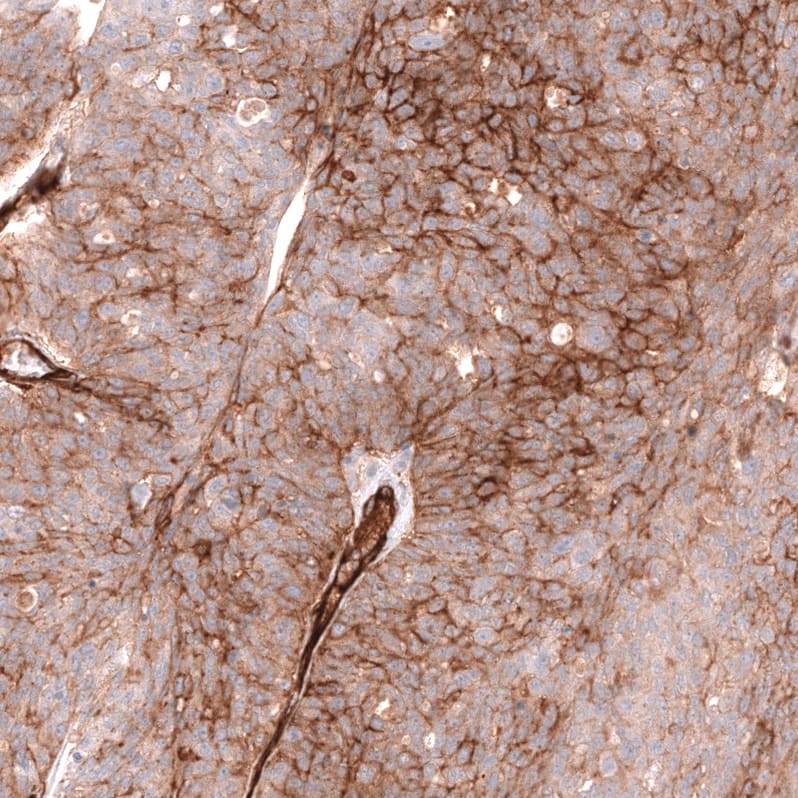

Staining of human malignant melanoma shows moderate membranous positivity in tumor cells.